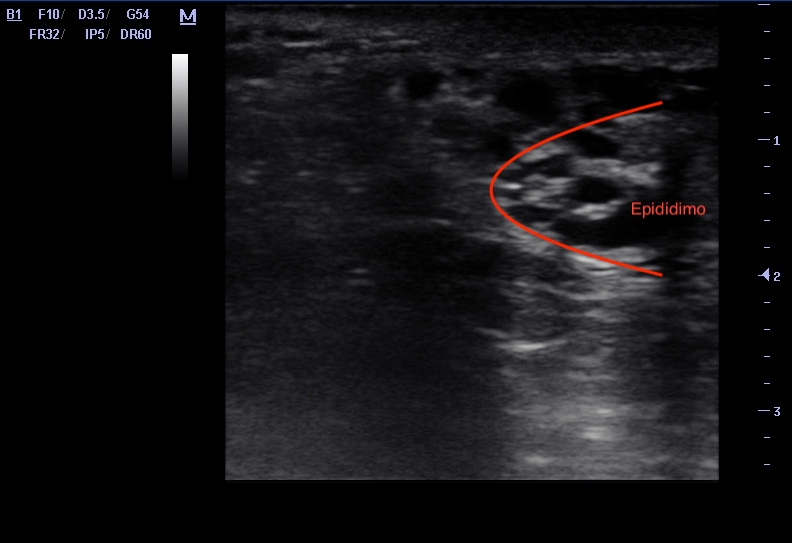

Se observa una imagen hiperecoica en 1/3 medio pared anterior de testículo derecho compatible con calcificación que deja sombra posterior, bien delimitada y sin imagen adyacente hipoecoica ni heterogénea. Además, se observa imagen en panal de abeja en epidídimo, que sugiere ectasia tubular de rete testis.

Ectasia tubular de rete testis y calcificación inespecífica de testículo derecho.